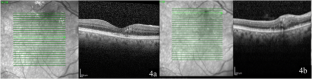

Fig. 4